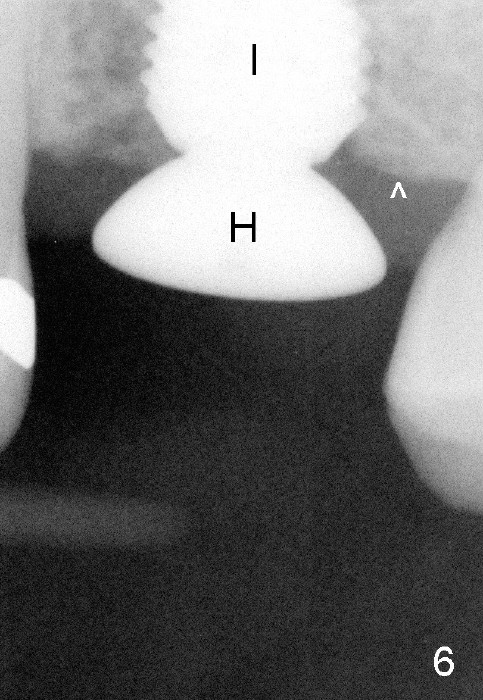

A 45-year-old man has lost the tooth #14 for a while (Fig.1); bone height is 5.4 mm. An extra wide and short implant is planned. Torus palatinus is large, suggesting that bone density should be high. A 6 mm tissue punch is chosen, but it is placed more palatal. If it were placed in the middle of the ridge, there would be no buccal keratinized gingiva (incision may avoid this issue). Additionally, the buccal portion of punch is made incomplete so that there is pedicle on the buccal side when the flap is raised (Fig.4,8: F). It is expected that the excess portion of keratinized tissue will form thick gingiva buccally. Osteotomy proves that bone is dense (Fig.2 (4.5x11 mm tap). Typical sinus lift is finished with placement of 6.4x6 mm (extra wide) bone-level implant (Fig.3, >55 Ncm). Following further torque, Fig.4 shows that the implant (I) is sub-gingival (<). Bitewings are taken to confirm that the implant plateau is at the crestal level (Fig.5,6 ^). PA shows sinus lift (Fig.7 *). The lingual aspect of the implant and healing abutment (H) is further bone grafted and covered by collagen dressing (Fig.8 *). The wound is protected with perio dressing. When the latter dislodges 7 days postop, the collagen dressing and bone graft are lost as well (Fig.10), while the buccal flap remains vital (Fig.9). The lingual exposed plateau should be able to heal normal. The collagen dressing should have been fixed in place by suture or as simple as a dental floss. There is mild nasal hemorrhage 1-2 days postop, possibly related to sinus membrane perforation and inability of Collagen Dressing to cover the perforation and contain the bone graft. When the patient returns for #9 implant placement in 3 weeks postop, the buccal flap reduces in size (Fig.11 *), while the palatal wound has healed with minimal exposure of the implant (Fig.12). Sinus graft remains in place 3 months postop (Fig.13); the buccal flap appears to have incorporated into a part of the gingiva (Fig.14). The bone density of the sinus lift appears to increase 10 days later when an abutment is placed (Fig.15 *). Although oral hygiene is pristine, there is apparent crestal bone resorption 12 months (Fig.16) and 20 months (Fig.17) post cementation, probably due to unfavorable crown/implant ratio and bruxism as well as pre-implantation bone loss (Fig.18,19). In contrast, an immediate implant in the same patient avoids pre- or post-implantation bone loss. In fact both the soft (Fig.20) and hard (Fig.21) tissues remain healthy 2 years 8 months post cementation. The sinus lift remains 3 years 8 months post cementation (Fig.22), while the crestal bone loss persists. The patients keeps complains of food impaction distal associated with bad smell 4 years 1 month post cementation. In fact the distal proximal contact is within normal limit. The bad smell is probably due to crestal bone loss (Fig.23 (pan), 24 (CT) *) and periimplantitis. Bone graft, PRF and Cytoplast membrane will be needed and fixed in place with long healing screw. When the patient returns for crown redo, he also reveals floss related gingival hemorrhage. There is pain associated with palatal sulcus probing with light gingiva erythema. Review of CT coronal section shows possible palatal (Fig.25 P) bone loss (*).